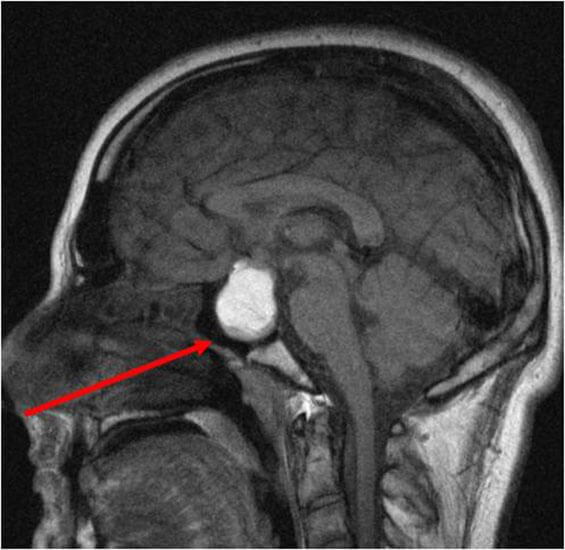

- Рентгенографию, компьютерную томографию, МРТ (позволяет выявить аденомы диаметром менее 5 мм), ангиографию для визуализации новообразований.

Врачи отмечают, что опухоли гипофиза могут проявляться разнообразными симптомами, включая головные боли, нарушения зрения и изменения в гормональном фоне. Эти проявления часто приводят пациентов к эндокринологам и неврологам, что подчеркивает важность ранней диагностики. Для подтверждения диагноза специалисты рекомендуют проводить магнитно-резонансную томографию, которая позволяет точно визуализировать опухоль и оценить её размеры. Лечение опухолей гипофиза может включать хирургическое вмешательство, радиотерапию и медикаментозную терапию, в зависимости от типа и стадии опухоли. Врачи подчеркивают, что индивидуальный подход к каждому пациенту и мультидисциплинарная команда специалистов играют ключевую роль в успешном лечении и восстановлении.